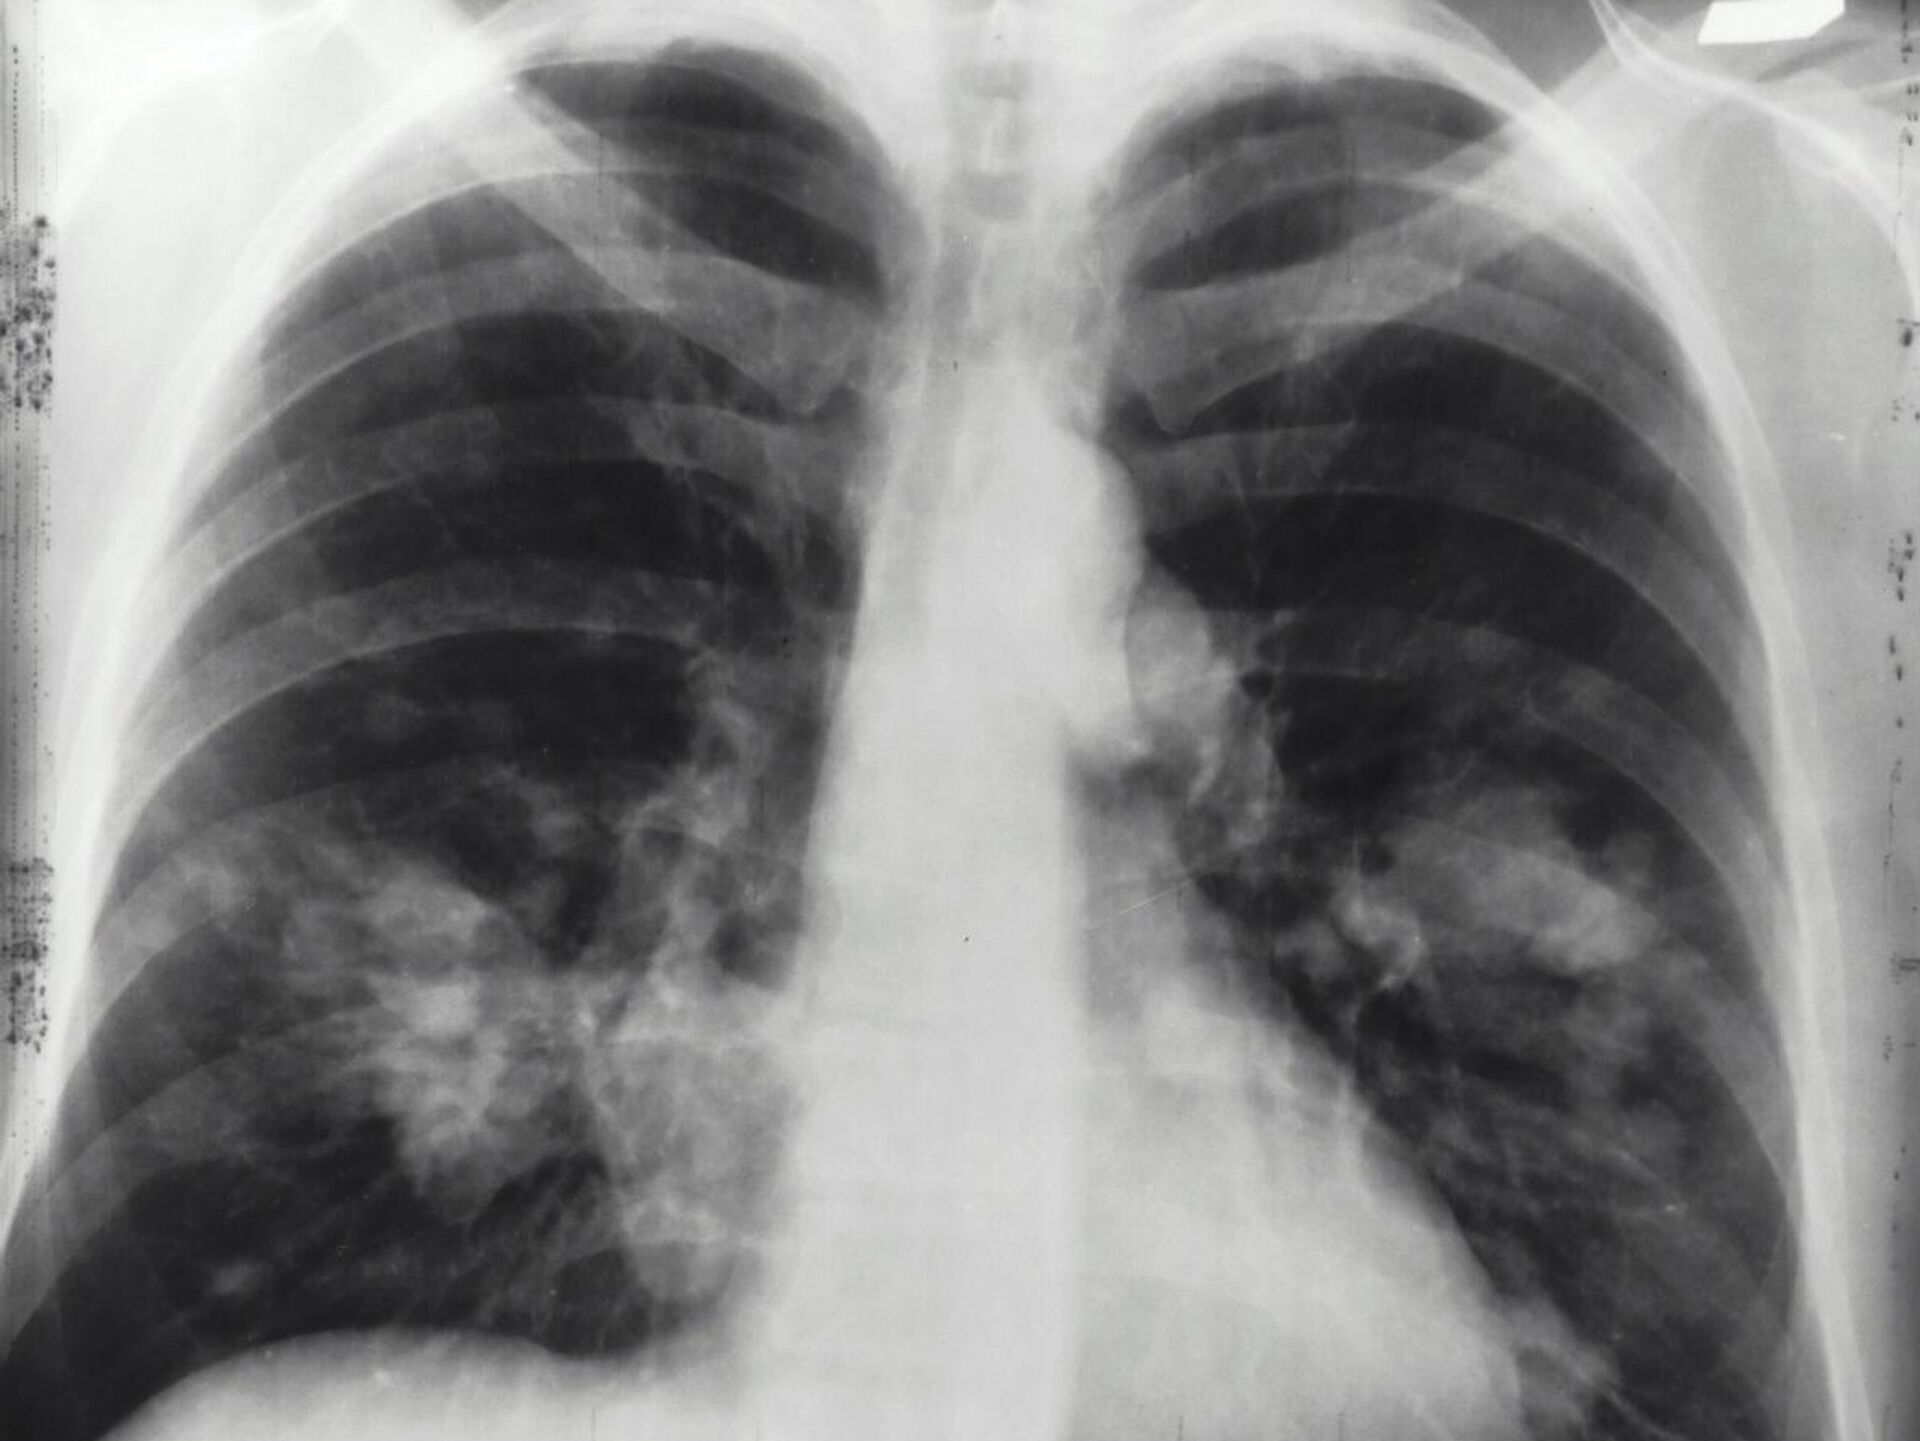

21:23 GMT 15.02.2025 (تم التحديث: 05:02 GMT 16.02.2025) كشفت دراسة جديدة عن تزايد مقلق في حالات الإصابة بسرطان الرئة بين غير المدخنين، خاصة في مناطق شرق آسيا وبالأخص في الصين، وهو من أكثر الأمراض فتكا، ويتسبب في ما يقارب مليوني وفاة سنويا.

ويُرجع الباحثون هذه الظاهرة، إلى تزايد مستويات التلوث البيئي، وتأثيره السلبي على الصحة العامة.

واستندت الدراسة إلى بيانات من المرصد العالمي للسرطان (GLOBOCAN) 2022، بالإضافة إلى سجلات سابقة تغطي الفترة بين عامي 1988 و2017، والتي أظهرت أن سرطان الغدة الدرقية هو النوع الأكثر انتشارا من سرطان الرئة عالميا، إذ يمثل 45.6% من الحالات لدى الرجال، و59.7% لدى النساء، ويعد هذا النوع من السرطان أكثر شيوعا بين غير المدخنين، على الرغم من إمكانية ارتباطه بالتدخين أيضا، وفقا

لموقع "Science Alert".

كما كشفت الدراسة عن اتجاه متزايد في حالات سرطان الرئة بين الأشخاص الذين لم يدخنوا أبدا، مما يستوجب التعامل مع هذه الظاهرة بجدية، إلى جانب الجهود المستمرة لمكافحة التدخين وتقليل معدلاته عالميا.

وأكد الباحثون أن سرطان الرئة لدى غير المدخنين، أصبح في الوقت الحالي هو السبب الخامس الأكثر شيوعا للوفيات المرتبطة بالسرطان على مستوى العالم، وهو يظهر بشكل شبه حصري على هيئة سرطان غدي، ويُلاحظ بشكل أكبر لدى النساء والسكان الآسيويين.

وخلصت الدراسة إلى أن أحد الأسباب الرئيسية لهذا الاتجاه التصاعدي، هو ارتفاع مستويات تلوث الهواء، إذ أثبتت العديد من الدراسات السابقة وجود علاقة وثيقة بين سرطان الغدة وتلوث الهواء.

وبرزت مناطق شرق آسيا، خاصة الصين، كأكثر المناطق تأثرا بسبب رداءة جودة الهواء فيها، مما يزيد من خطر الإصابة بهذا النوع من السرطان.

وبينما تتراجع نسبة المدخنين عالميا، فيبدو أن التلوث البيئي بات يشكل تهديدا صحيا متزايدا، إذ يتبين أنه عامل لا يرتبط باختيارات نمط الحياة الشخصية، بل يرتبط بالممارسات البيئية العالمية التي تؤثر على جودة الهواء الذي نتنفسه جميعا.

وشدد معدو الدراسة على أهمية جمع البيانات وتحليلها باستمرار لفهم كيفية تطور سرطان الرئة بمرور الوقت، مما قد يساعد العلماء في تطوير استراتيجيات أكثر فاعلية لمواجهة هذا المرض القاتل، وأوصت الدراسة بضرورة تنفيذ سياسات صارمة للحد من تلوث الهواء، إلى جانب تعزيز حملات مكافحة التدخين، بهدف الحد من انتشار المرض، وحماية الأجيال القادمة من خطره المتزايد.